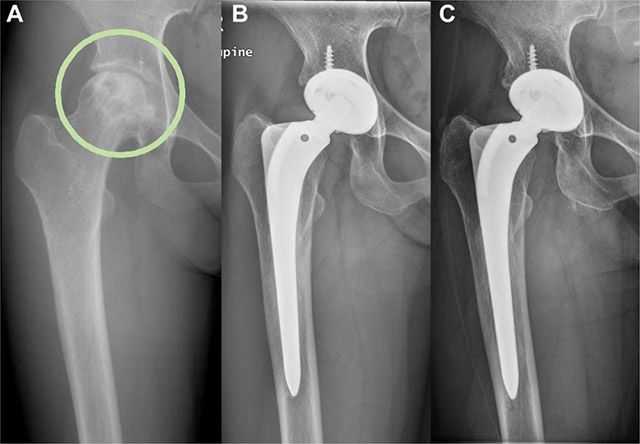

서울대병원 정형외과 김홍석·유정준 교수팀은 3세대 세라믹 인공고관절 전치환술의 장기 안정성을 확인하기 위한 장기 추적 관찰 결과, 우수한 안정성을 확인했다고 13일 발표했다.

연구팀은 1997년 11월부터 1998년 4월까지 3세대 세라믹-세라믹 관절면 인공고관절 전치환술을 받은 57명을 25년 이상 추적 관찰했다.

분석 결과, 25년간 인공고관절 교체 또는 재수술 없이 장치를 유지한 비율(생존율)은 96.3%였다. 또한, 통증·운동범위·걸음걸이 등을 종합하여 고관절 기능을 평가하는 해리스 점수는 평균 90.1점으로 우수했다.

영상 분석 결과, 주요 합병증인 인공관절 주변부 골용해(관절면 마모 및 감염 등으로 인하여 뼈조직이 파괴되는 현상) 및 인공관절 해리(뼈와 인공관절이 분리되는 현상)도 발견되지 않았다.